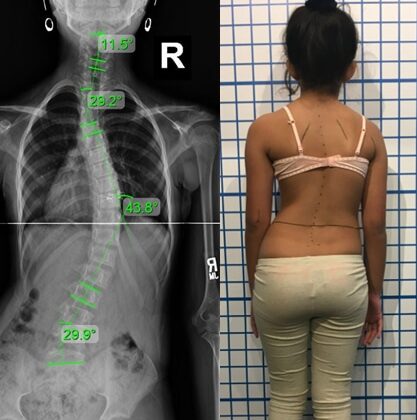

الانحناءات الأكبر من 45–50 درجة قد تستمر في الازدياد ببطء حتى بعد توقف النمو.

الانحناءات التي تبدأ بـ 20 درجة أو أكثر أكثر عرضة للزيادة مقارنة بالانحناءات الصغيرة.

الأشعة الدورية لقياس زاوية كوب هي الطريقة الوحيدة لمعرفة التطور.

هل جراحة اعوجاج العمود الفقري ضرورية؟

لا، نسبة كبيرة من الأطفال يتجنبون الجراحة عند التدخل المبكر، خاصة قبل الوصول لـ 40 درجة.